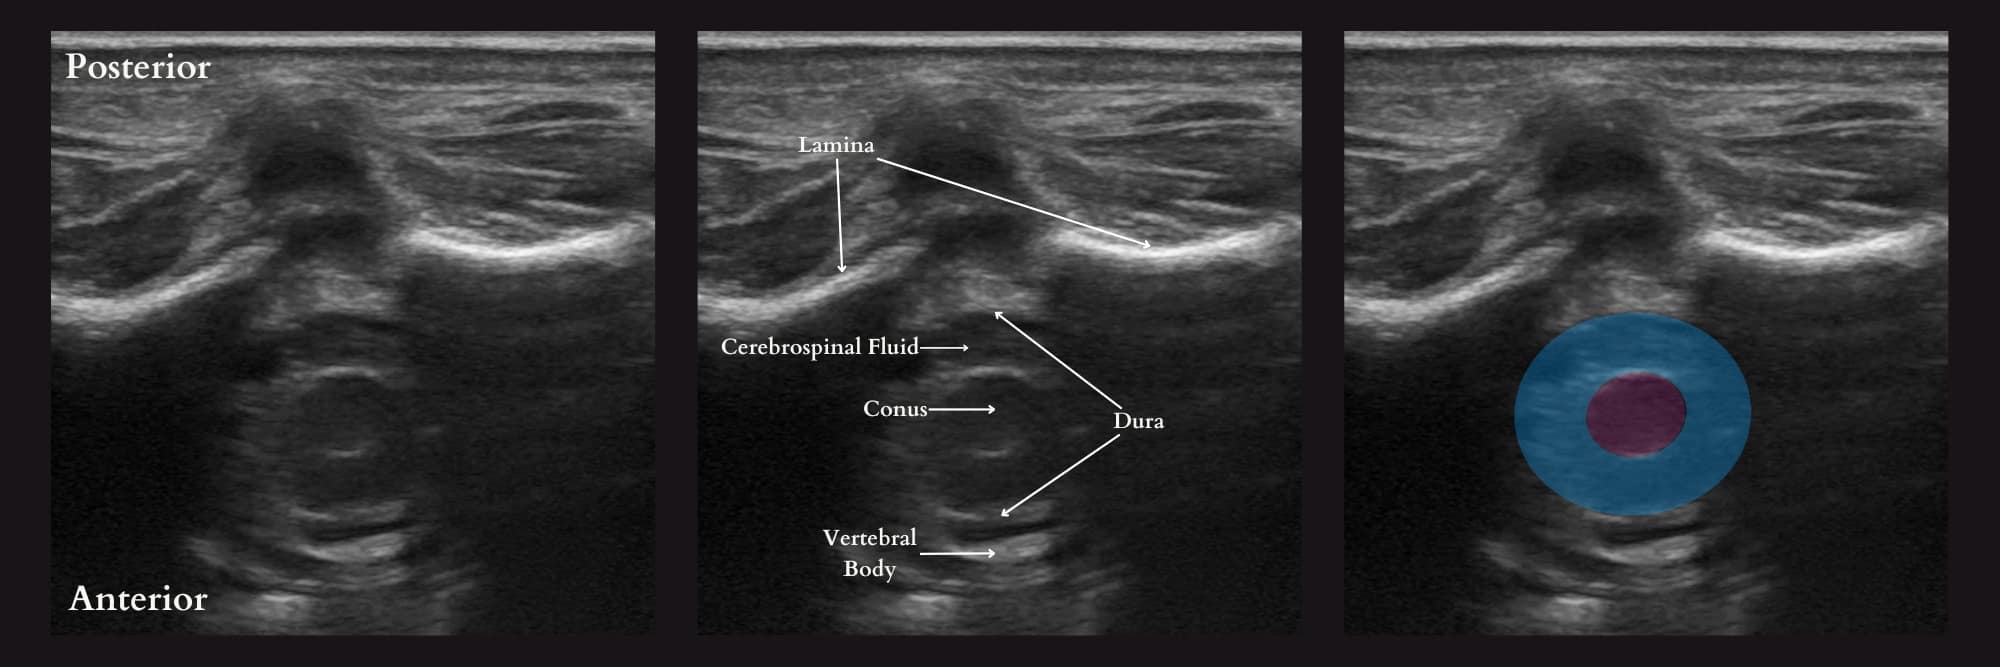

The technique for spinal anesthesia placement in infants has not changed for over 130 years.21 The typical approach involves a landmark-based technique using palpation of the vertebral interspaces and blind advancement of the needle into the intrathecal space. However, with the advancements in ultrasound technology, a growing body of literature supports using ultrasound imaging to improve infant success rates. Ultrasound offers excellent views of the infant’s spine due to its lower bone ossification and higher water content (Figure 12). However, the effect of ultrasound on infant LP success rate is unclear and may vary depending on the sonographer’s experience. In contrast, continuous ultrasound guidance rather than the preprocedural ultrasound has been associated with a much higher first-pass success rate. The primary reason is that it has the advantage of needle redirection toward a visible target, limited needle advancement into undesirable structures, and visualization of the injectate at the desired target location in the intrathecal space.21-24

Reproduced with permission from baby-blocks.com